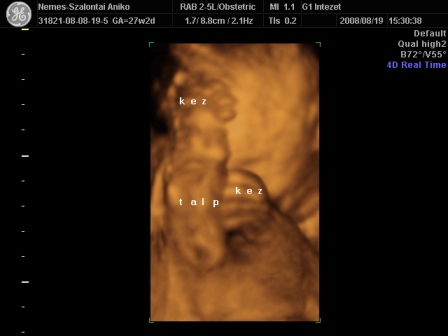

Én Óbudán a G1 intézetben voltam 4D-n. Régen ők voltak a Schöpf-Méreiben. Nagyon-nagyon kedvesek voltak. Nem kaptam letolást, mert késtünk sajnos a dugó miatt. Mondták telefonban, hogy ne idegeskedjek, csak menjünk :D .

Egy nagyon kedves hölgy vizsgált. Mindent megtett, hogy a lehető legjobb képet tudja csinálni a piciről. Nem volt könnyű dolga, mert végig háttal volt, a pofikája előtt volt a köldökzsinór, a két keze és az egyik talpa :lol: . Tornász lesz a gyerek :D . Viszont a fiússágát rögtön megmutatta. Összesen fél órás volt a vizsgálat. A picur méretei teljesen megfelelnek annak, ahány hetes vagyok. Eszerint nov. 9. és 16. között születik. Nem tudom, hogy a saját dokim, honnan szedett 20-át? Mindegy, úgyis akkor jön, amikor jönnie kell. A súlya a picinek 1103 g :) . Jó a szívhang és a köldökzsinór véráramlása is.

Készült DVD az egész vizsgálatról. 4 fényképet kinyomtattak, amit mi választottunk ki. És feltöltötték a honlapjukra az összes képet, amit egy kapott kóddal megnézhet bárki 30 napig. Így a távoli-külföldi rokonok is rögtön láthatják a bébit :).

Szóval teljesen elégedett voltam. Nekem a vizsgálat (hála a babaszobának) ingyenes volt, amúgy 13e Ft.

És a tornász pozíció